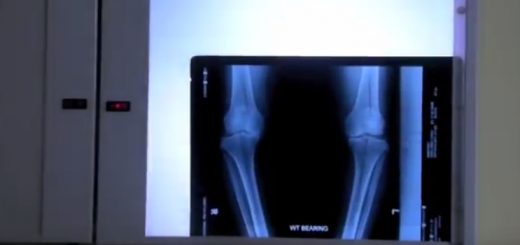

This patient was suffering from chronic lower back pain that could not be resolved for many years. After an acute episode, he came to our clinic and we managed to help him with Gonstead Chiropractic care. Watch the video to learn more!